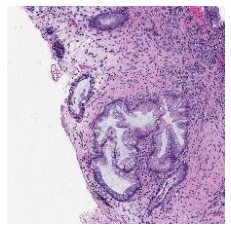

2.1 Embedding Knowledge From Privileged Image Modalities

We first demonstrate that TriDeNT ♆ is highly effective for improving the quality of representations in the primary encoder by distilling privileged information from immunofluorescence (IF) images to H&E stained images (Figure 2 and Table S6). Models are trained on the SegPath dataset [22], which consists of eight subsets of H&E images paired with an image derived from the IF stain of a consecutive slice for one of eight antibodies. Evaluation is performed on four standard computational pathology tasks (see Section S2 for full details). We find that the model significantly increases performance by up to 101% compared to a privileged baseline model. TriDeNT ♆ retains not only the useful features shared between inputs, but also the features which are only present in the primary data, leading to better performance on all evaluated tasks. Even in cases where the privileged data does not appear to significantly improve performance, such as staining with CD235a, TriDeNT ♆ still achieves comparable performance, as it obtains a strong supervisory signal from the additional H&E branch. This is in contrast with the privileged Siamese setting, where it is clear that the pairing can cause a seismic drop in classification accuracy if the privileged data is not informative for the task being evaluated.

To further analyse the learned representations, we produce UMAP projections of the latent space labelled with the tissue types for the NCT tissue type classification task, as shown for CD3CD20 and SMA in Figure 4(a), and for all SegPath stains in Figures S8 and S9. These figures make the reasons for the varying performance of the privileged Siamese model more apparent. For stains with better performing privileged Siamese models, such as SMA, the UMAPs are very similar between Siamese methods and TriDeNT, with well-differentiated tissue type clusters. In those with worse performance, such as ERG, the tissue types are poorly differentiated, often with only adipose and background forming distinct clusters from the other classes. On closer inspection, it is notable in these projections that TriDeNT ♆ produces more well-defined and separated clusters in general than Siamese networks. This is further evidenced in Figure S7, where TriDeNT ♆ is shown to identify clusters with overexpression of a given gene significantly more effectively than an unprivileged Siamese model.

We also analyse the activation maps for each model using GradCAM as described in section S3. This offers more insight into the areas of the image which are contributing most heavily to the models’ representations. In Figure 4(b) we present some representative examples, however, a larger selection which was chosen at random is presented in Figures S10 to S25. The larger selection makes it easier to see the emergent patterns, including that privileged Siamese models tend to mainly identify features which are strongly present in both inputs, while unprivileged Siamese models tend to learn more diffuse features that are not specific to one cell phenotype or image region. TriDeNT ♆ incorporates both sets of features, learning both features specific to the privileged data and more the general features associated with unprivileged Siamese networks.

We can see in Figure 4(b) panel A that for ERG, the privileged Siamese model focuses almost exclusively on any nuclei which could be endothelial cells. As there are very few endothelial cells in the dataset, it could be an effective strategy to identify anything that could potentially be an endothelial cell to minimise the difference between the representations of the H&E model and the IF mask model. In the corresponding unprivileged Siamese image, we see that the model identifies some of these nuclei, albeit less strongly, but also focuses heavily on the other tissue and even the background, while strongly fixating on two spots of debris in the center of the image. This model has less ‘incentive’ to learn the weak features related to endothelial cells as these occur rarely and are not easy to detect, while more generic strong features such as the presence of connective tissue and the prevalence of background are more common and predictable from augmented images. We see that TriDeNT ♆ combines these two feature sets, strongly identifying nuclei while also identifying the connective tissue.

In panel C we see a similar pattern, with the privileged Siamese model fixating solely on the nuclei, while the TriDeNT ♆ model takes a more balanced approach. The unprivileged Siamese model appears to focus on a single cluster of nuclei while neglecting others, and similarly identifies an area of fibroblasts with its distinctive pattern but does not others.

In contrast to panels A and C which represent models with poor privileged Siamese results, panels B and D represent models whose privileged Siamese results were comparable to both TriDeNT ♆ and even the supervised baseline. It is therefore interesting to note that there are far more similarities between the privileged Siamese and TriDeNT ♆ models in both cases. Particularly in panel B, TriDeNT ♆ and the privileged Siamese model return virtually identical heatmaps, with both strongly identifying epithelial nuclei and neglecting the same areas of connective tissue. The unprivileged model in this case appears to focus solely on the centre of the image, giving a significantly different heatmap to the other panels.

Panel D again shows the previous pattern, with the privileged Siamese model identifying the features strongly present in the privileged data – fibroblasts – while neglecting the nuclei present. TriDeNT ♆ also strongly identifies the connective tissue, but, unlike the privileged Siamese model, does not completely neglect the nuclei. The unprivileged Siamese model primarily identifies background, and does not appear to identify the nuclei in this example.

S1.1 Histology

To analyse tissue samples, pathologists take slices of tissue around 5m thick to be analysed under a microscope. To make it easier to identify different structures, the slide is typically stained with chemicals that bind tightly to different components of the sample, dying them different colours. By far the most common staining method used in histopathology is haematoxylin and eosin (H&E) staining. Haematoxylin stains components that are rich in nucleic acids, such as nuclei and ribosomes, while Eosin stains common protein structures pink, such as connective tissue, collagen, and the cytoplasm [54].

Immunohistochemistry is an ancilliary staining technique often used in medical diagnosis, which works by using an antibody to target specific proteins in tissue. Secondary chemical processes are coupled to the antibody to produce a colour, making it much easier to identify their presence and location within tissue. There are many different antibodies used which each target a specific protein or protein type. Common examples of antibody targets include cytokeratins, which are found in epithelial cells, CD3, CD4, and CD20, which are found in various types of immune cells, and smooth muscle actin (SMA), which is found in myofibroblasts [55].

Typically these stains are highly informative about one particular protein of instance, but lack the generality of H&E staining. Consequently, they are primarily used as secondary sources of information to assist with research or diagnosis.

While H&E staining is the routine protocol for tissue analysis, pathologists usually rely on IHC or IF staining to obtain information about the locations of individual proteins, which may aid further investigation or confirm their diagnoses. IHC and IF stains therefore contain highly specific information about a particular protein, so add useful information beyond that which can be readily identified with H&E staining. While this is necessary for human pathologists to identify features which cannot be easily identified by eye in the generic H&E stains, for example separating the identities of individual epithelial, endothelial, myeloid cells and lymphocytes, it has been shown that neural networks can accurately reproduce many of these stains from only H&E [39]. It would be tempting to conclude, then, that this is a solved problem, and researchers should simply use these models to produce representations of H&E patches which contain features relevant to IHC or IF stains. Unfortunately, this has been shown to perform poorly [19], as image to image translation models are restricted to learning very fine grained information, such as the exact locations of nuclei, at the expense of the types of low-redundancy coarse grained features which are learned by self-supervised Siamese networks.

Nevertheless, the results of these works imply that much or all of the useful information in IHC and IF stains can be predicted from H&Es. We investigate how representation are affected by distilling information from IHC and IF stains into models of H&E stains, evaluating both brightfield IHC images and thresholded IF images.

S2.1 SegPath

SegPath [22] is a large pan-cancer dataset containing 8 subsets corresponding to 8 different IF stains with paired H&E stains, which are detailed in Table S1. Stains were performed individually on each slide, not multiplexed, and H&Es were obtained from the same section as the IF by initially staining with H&E, then washing the slides and restaining with the IF stain. Different slides were used for each stain, so there is inter-subset variability between the image features present in the subsets. Slides were tissue microarrays featuring samples from cancer types including glioma, meningioma, ependymoma, kidney renal clear cell carcinoma, lung adenocarcinoma, lung squamous cell carcinoma, breast adenocarcinoma, gastric adenocarcinoma, colon adenocarcinoma, pancreatic adenocarcinoma, cholangiocarcinoma, hepatocellular carcinoma, esophageal squamous cell carcinoma, head and neck squamous cell carcinoma, urothelial tumors, bladder cancer, prostate adenocarcinoma, sarcoma, melanoma, uterine cancer, ovarian tumors, and testicular germ cell tumors.

We paired H&E images with corresponding thresholded IF images of the same (restained) patch from the SegPath dataset [22]. IF images were obtained by thresholding IF intensity, such that pixels with lower intensity than the cutoff were labelled 0 and those higher than the cutoff were labelled 1. For ease of computing and consistency of size with evaluation datasets, we resized each px image to px with linear interpolation, and split these into 16 px patches, and did the same for each corresponding mask. Each input was a tuple , with both and being px (pixel) patches from the same location on both the H&E and restained slides. Given that no evaluation was to be performed directly on the SegPath dataset, the train, validation and test sets were combined to increase the dataset size, with the number of patches for each stain after preprocessing detailed in Table S1.